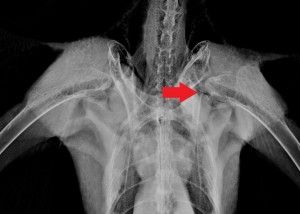

LATEST UPDATE ON RTH December 19 update Red-tailed Hawk #11-2361 was brought into the hospital on December 19 for a series of radiographs. The hawk was anesthetized for the x-rays. Dr. Adam reports that the hawk’s left shoulder – the main area of concern on the last set of radiographs – has not changed in the past two weeks. However, radiographs revealed boney changes in the hawk’s left elbow and carpus. The veterinary team went back to review all of the hawk’s radiographs since its September admission, and are concerned about this development. At this point, the team isn’t sure why this is happening, though it could be a result of the hawk’s initial shoulder injury and how it is holding its wing and flying. The left shoulder of the hawk is unchanged from the last set of radiographs: ![]() The developments in the hawk’s elbow and carpus are cause for concern: ![]() The hawk is scheduled for another set of radiographs in two weeks. Since the injury is not stable at the moment, the hawk is not a candidate for release yet – the team will need to wait and see what sort of developments occur in two weeks’ time. |